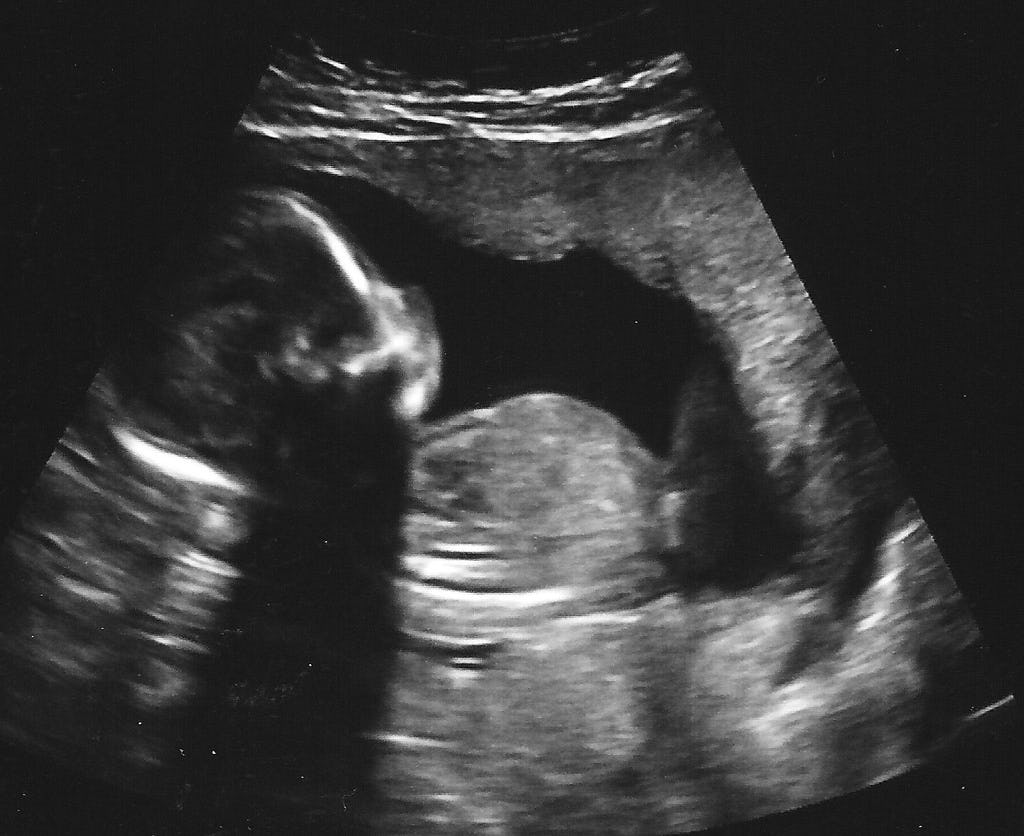

3. Fetal Development Nurse Key How To Have A Baby Without Uterus Written by bhavyajyoti chilukoti | updated : — when a woman with all of her reproductive organs gets pregnant, it's because an egg drops from her ovaries. hence, a woman who has had a hysterectomy cannot have babies in the normal way. What happens when a woman doesn't have uterus? — the short answer is no, you. How To Have A Baby Without Uterus.